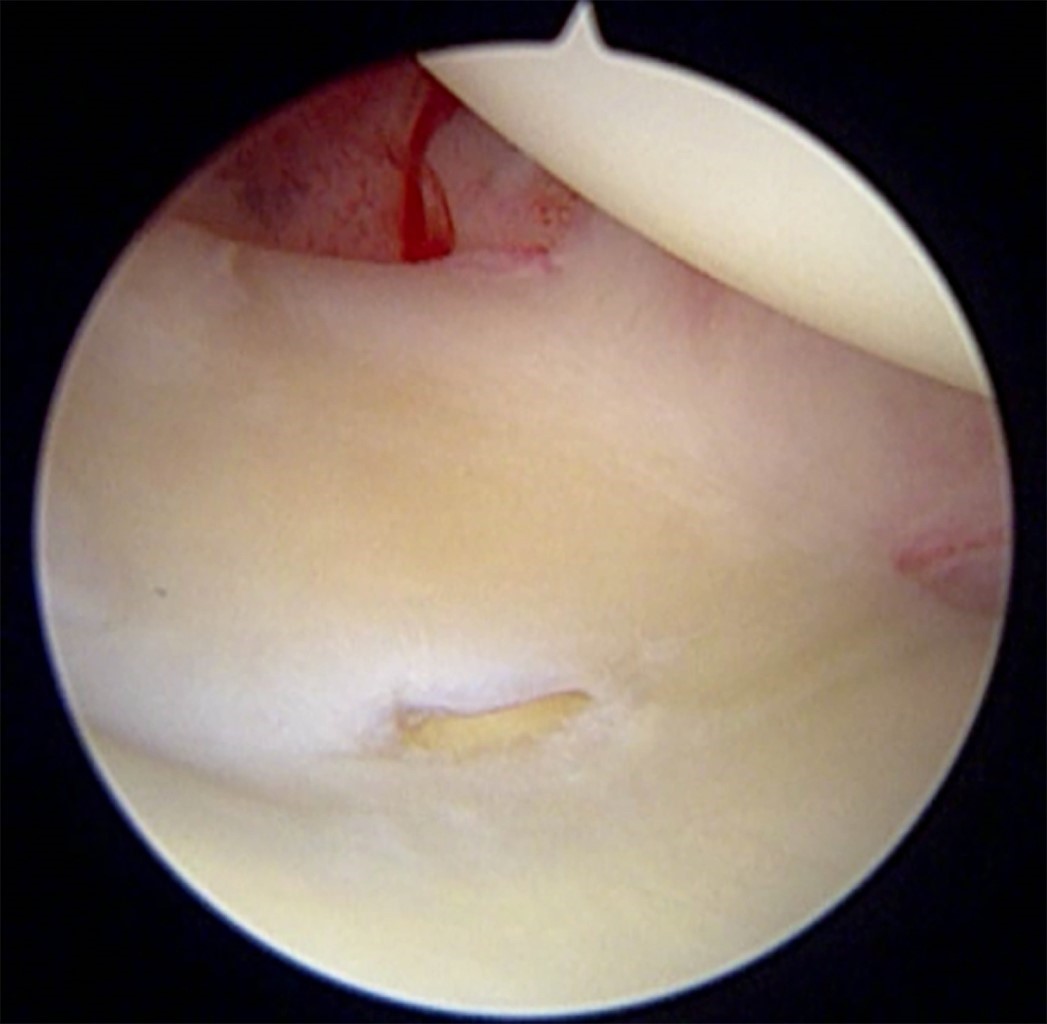

Se incluyeron a todos los pacientes que cumplieron con los criterios de inclusión de los que se tiene registro para este estudio, aunque la muestra fue pequeña. Asimismo, se decidió agotar todas las opciones terapéuticas no invasivas antes de pasar a la reparación quirúrgica mediante artroscopía de muñeca, por lo que existe una mayor ventana de tiempo entre la resonancia magnética y la artroscopía de muñeca, pudiendo dar espacio a una mayor cantidad de lesiones y/o gravedad de estas. En la Figura 2 se observa lesión del ligamento escafosemilunar observada mediante resonancia magnética y artrosocopia de muñeca en el mismo paciente. En la Figura 3 se observa lesión del fibrocartílago triangular Palmer 1D. Y en la Figura 4 se observa lesión del ligamento radioescafogrande.

Figura 2

Figura 3